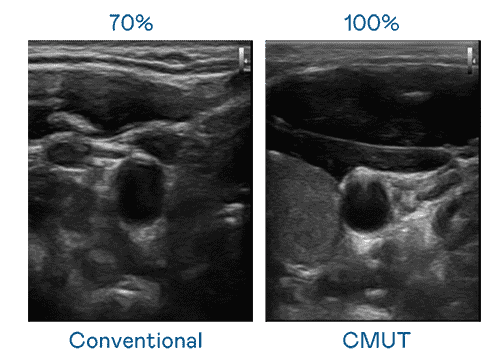

CMUT 技术是一种用电容式微机电元件来产生超音波讯号的技术。。。与传统 PZT 压电式技术相比,,CMUT 频宽增加 30%,,更宽频的超音波讯号让影像解析度大幅提升,,,是实现高影像品质医疗超音波扫描、、、、促进精准医疗发展的关键技术。。

大频宽带来超清晰影像

超音波影像的解析度高低,,,,首先取决于探头能发出的讯号频宽。。。万利 CMUT 可提供高清晰的超音波讯号,,,,提供高频宽、、、、高灵敏度、、影像纹理细节更高的超音波影像,,,协助医护人员缩短影像判读时间及利用精准的医疗影像进行诊断。。。